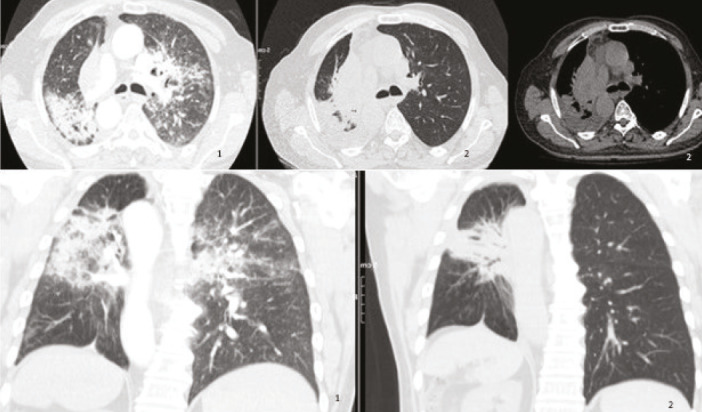

Can Pirfenidone and Nintedanib Be Alternative Treatment Options for Radiation Pneumonitis?

Abstract Image